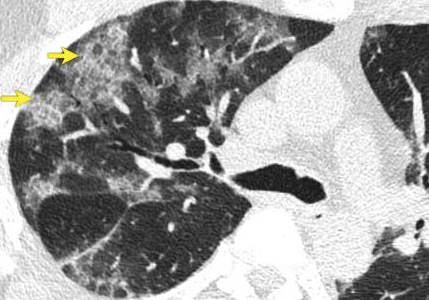

On cross sectional CT imaging of the lung, sometimes, you might see what is known as thickened interlobular and intralobular lines (opacities) in combination with a ground glass pattern. This CT finding is called crazy paving.